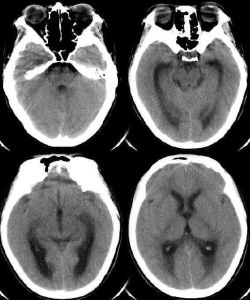

影像學檢查

腦部CT或MRI一般無異常。